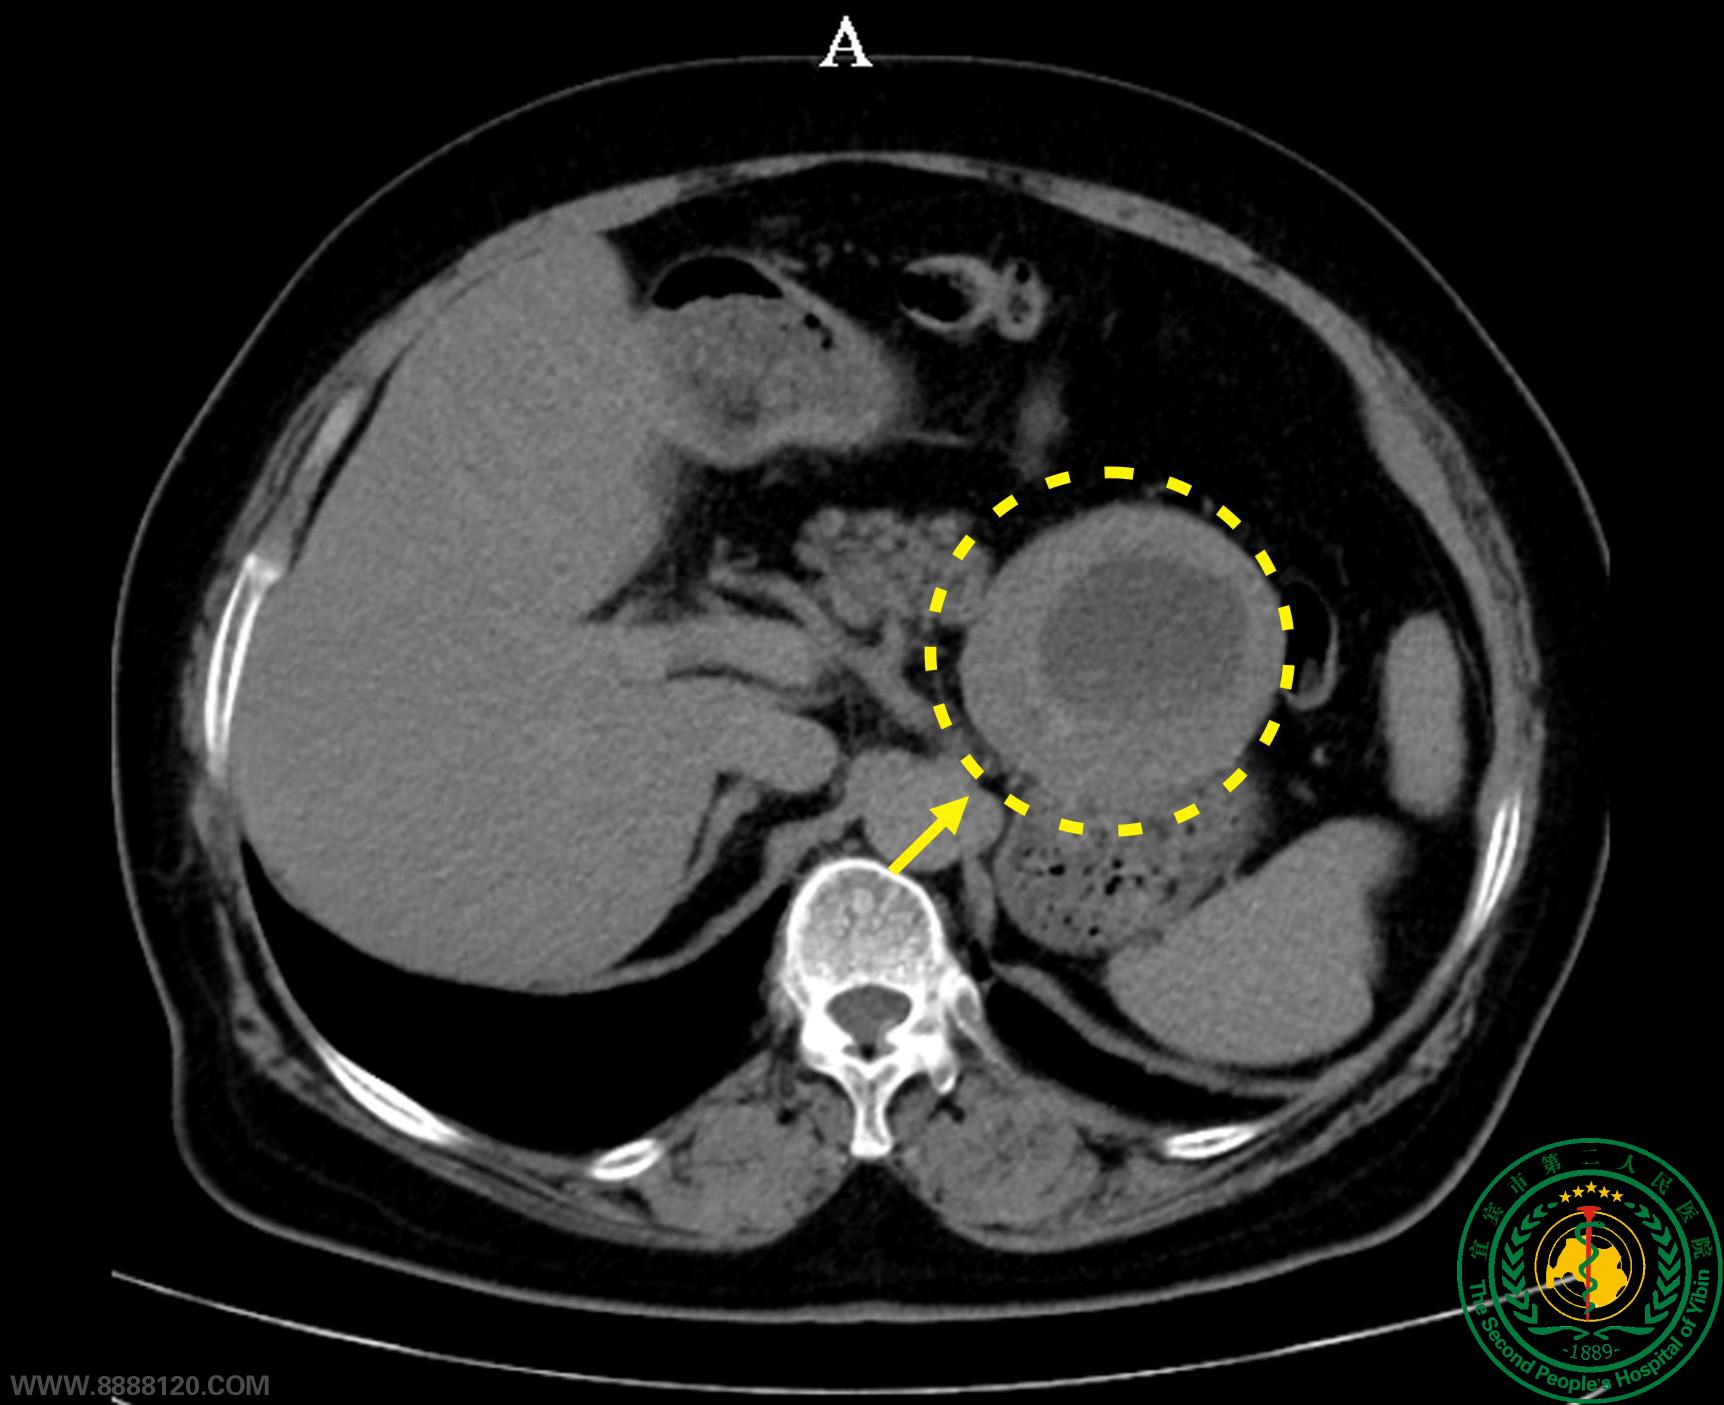

该患者74岁,体质指数BMI为32.6kg/m2(一级肥胖),因“发现胃周肿块1周”,经胃镜检查提示“胃体间质瘤”,于623日来我科治疗。CT检查提示:肿瘤位于左上腹(胃与胰腺、肾上腺之间),大小约8.0×7.1×7.9cm。经胃肠肿瘤多学科讨论后决定为其实施腹腔镜胃体间质瘤切除术。手术中发现患者肿瘤位于胃后壁,肿瘤多支血供且与胃左血管分支分界不清靠,与胰腺、肾上腺致密粘连。遂为其实施了完全腹腔镜胃体间质瘤切除、经自然腔道取标本术。术后在快速康复流程指导下,第2天恢复流质饮食、下床活动,第7天顺利康复出院。